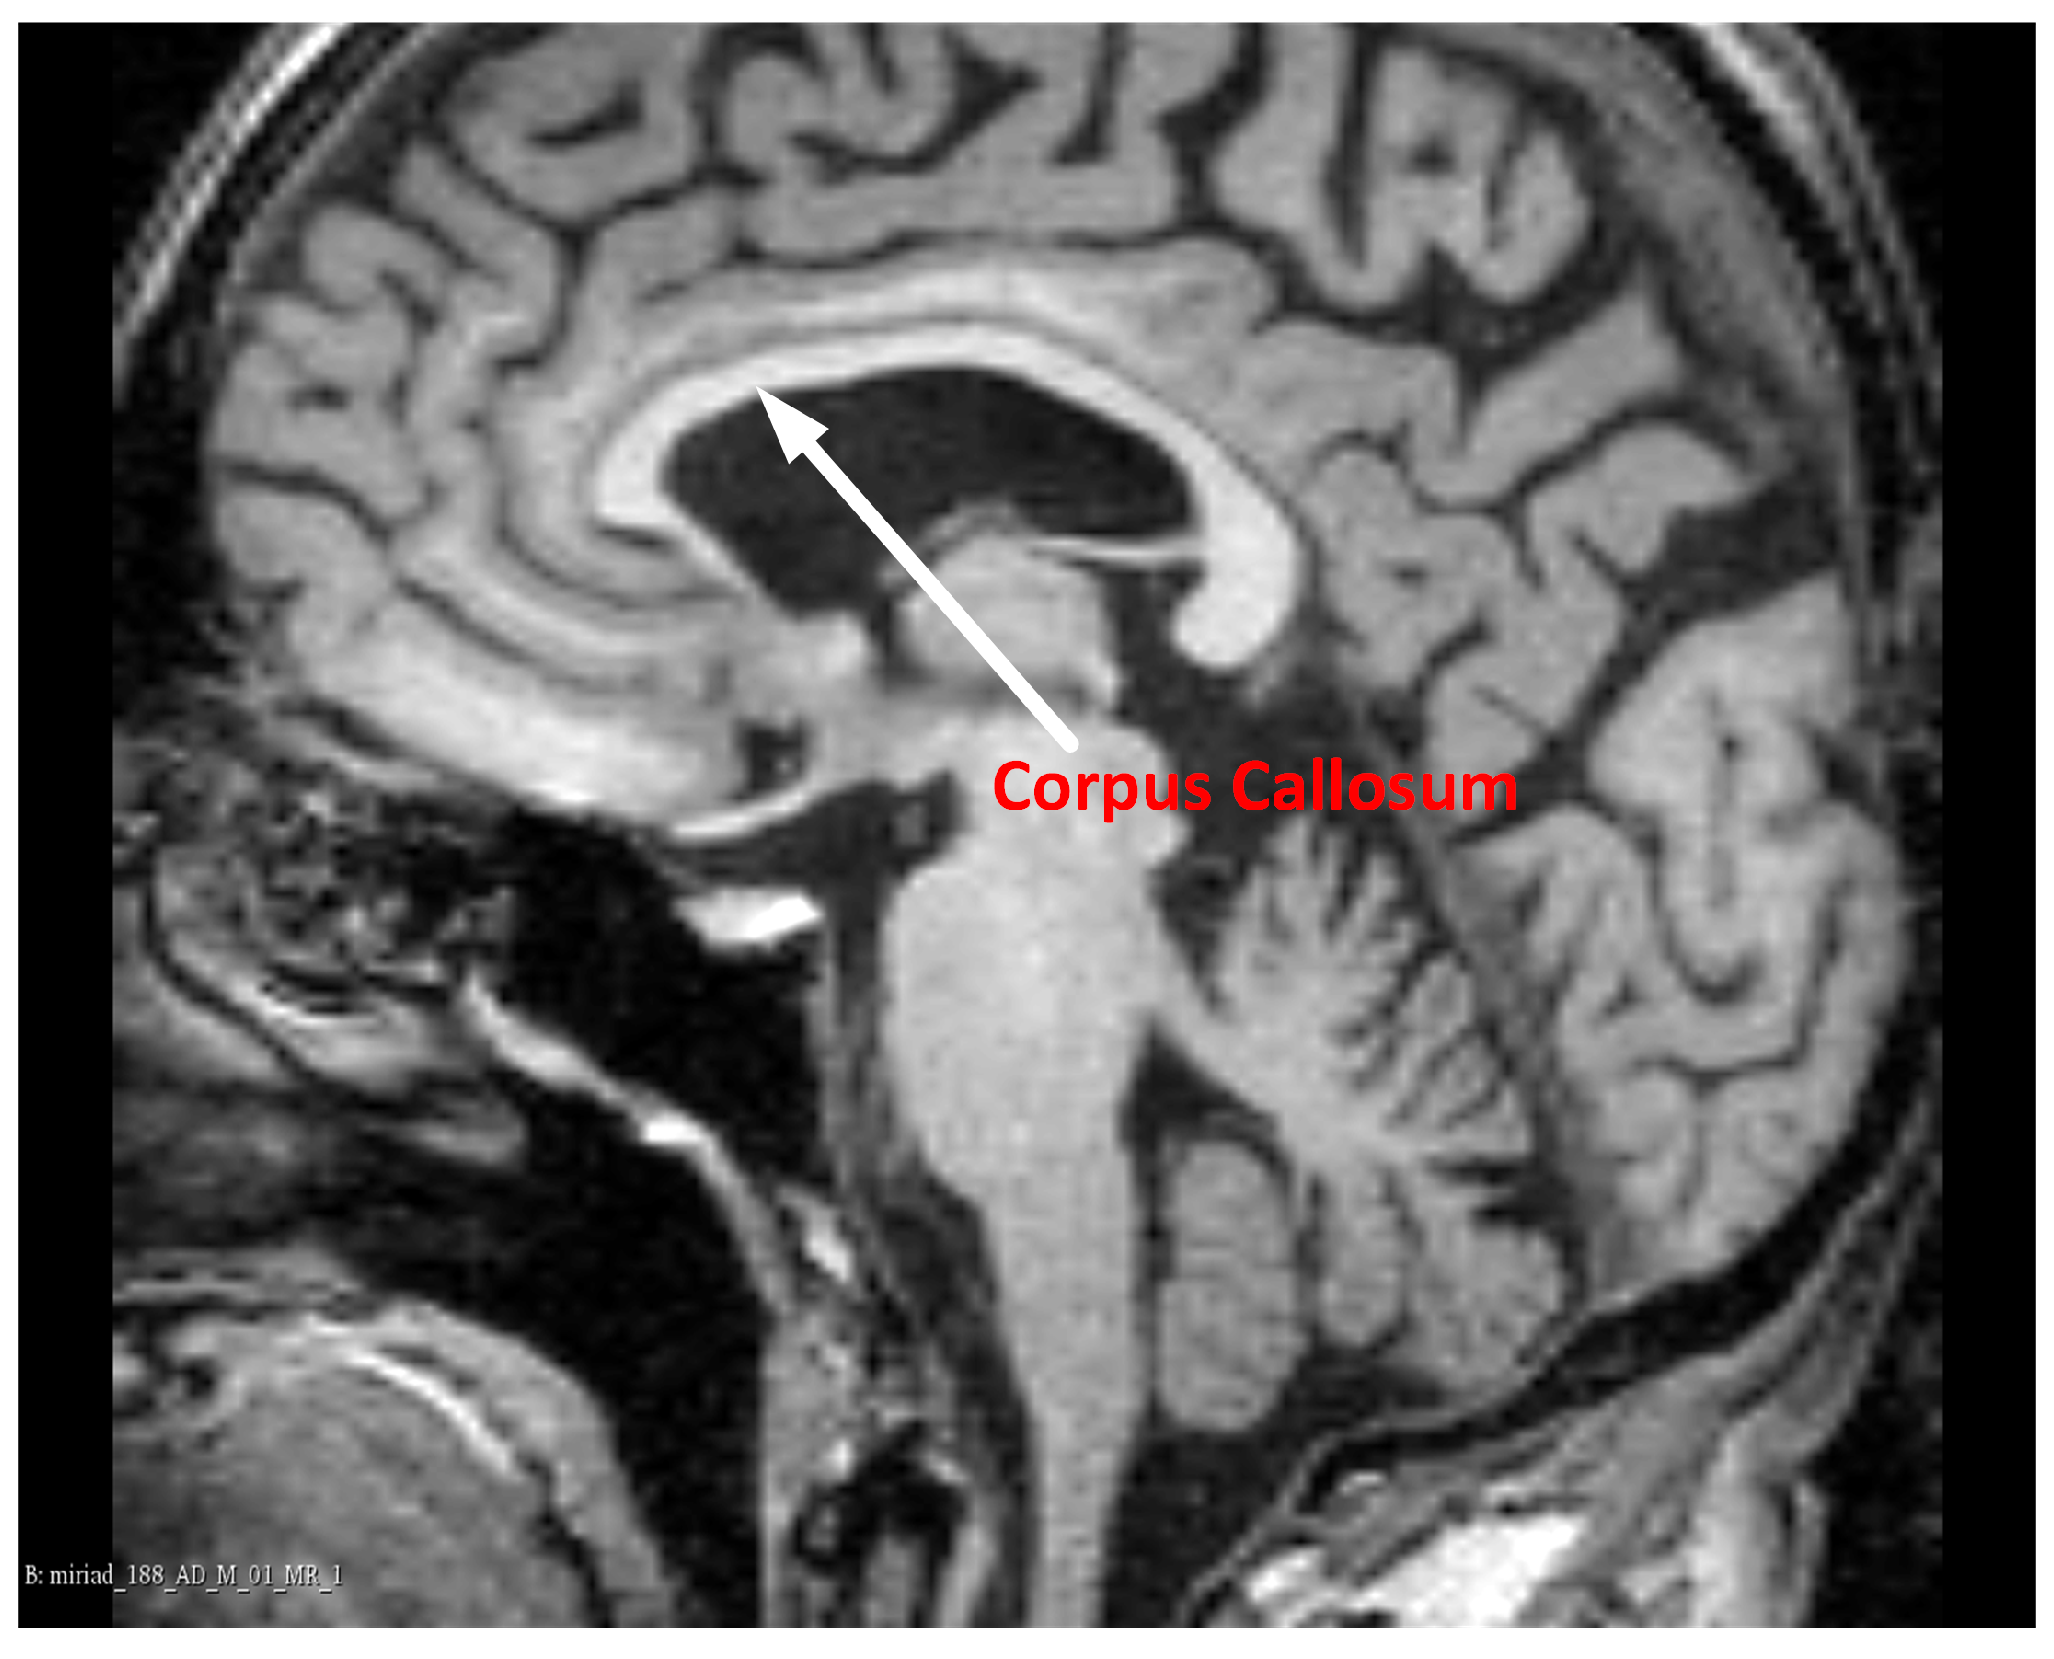

Showing position of corpus callosum in midsagittal view of MRI (arrow What Techniques Are Used To View Or Measure The Corpus Callosum a variety of techniques have been introduced to accurately segment, align and measure the callosum ( bookstein, 2003;. various imaging techniques such as us, ct, and mri are used to image the normal anatomy, to reveal and characterize. in the literature, several authors have used different techniques to estimate cc size and growth. the corpus callosum. What Techniques Are Used To View Or Measure The Corpus Callosum.